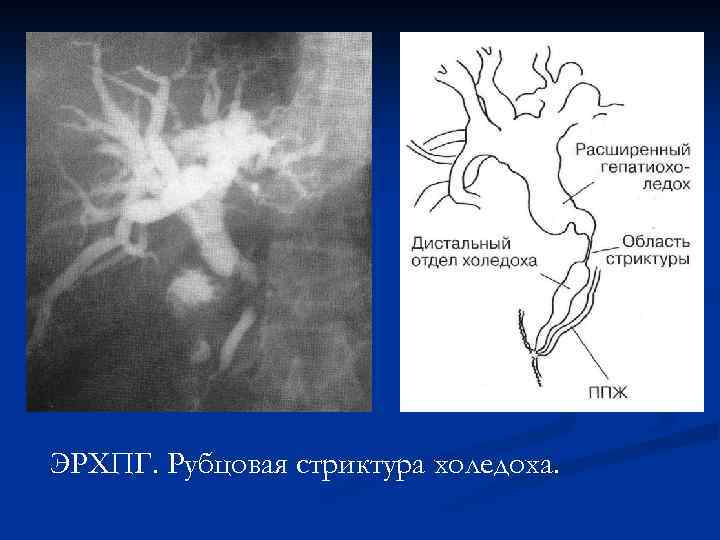

ЭРХПГ. Рубцовая стриктура холедоха.

ЭРХПГ. Рубцовая стриктура холедоха.